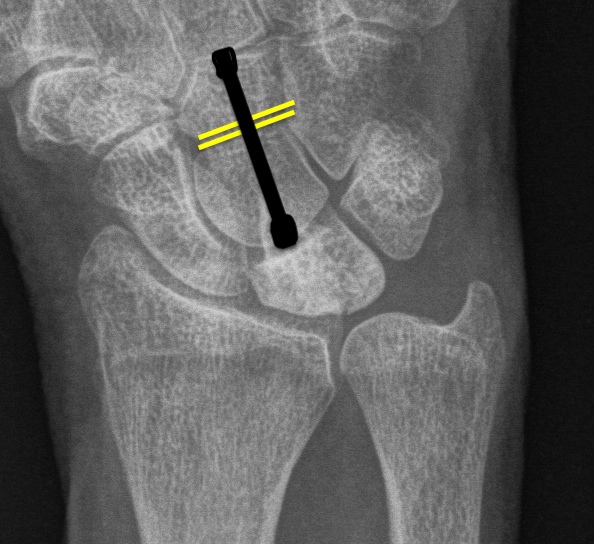

Ulna Variance

Supination and pronation alter variance

90 / 90 view (elbow 90° / shoulder abducted 90°)

- neutral supination / pronation

- PA film with wrist in neutral

- line from lunate fossa and ulna head

Ulna neutral

Ulna positive

Ulna negative